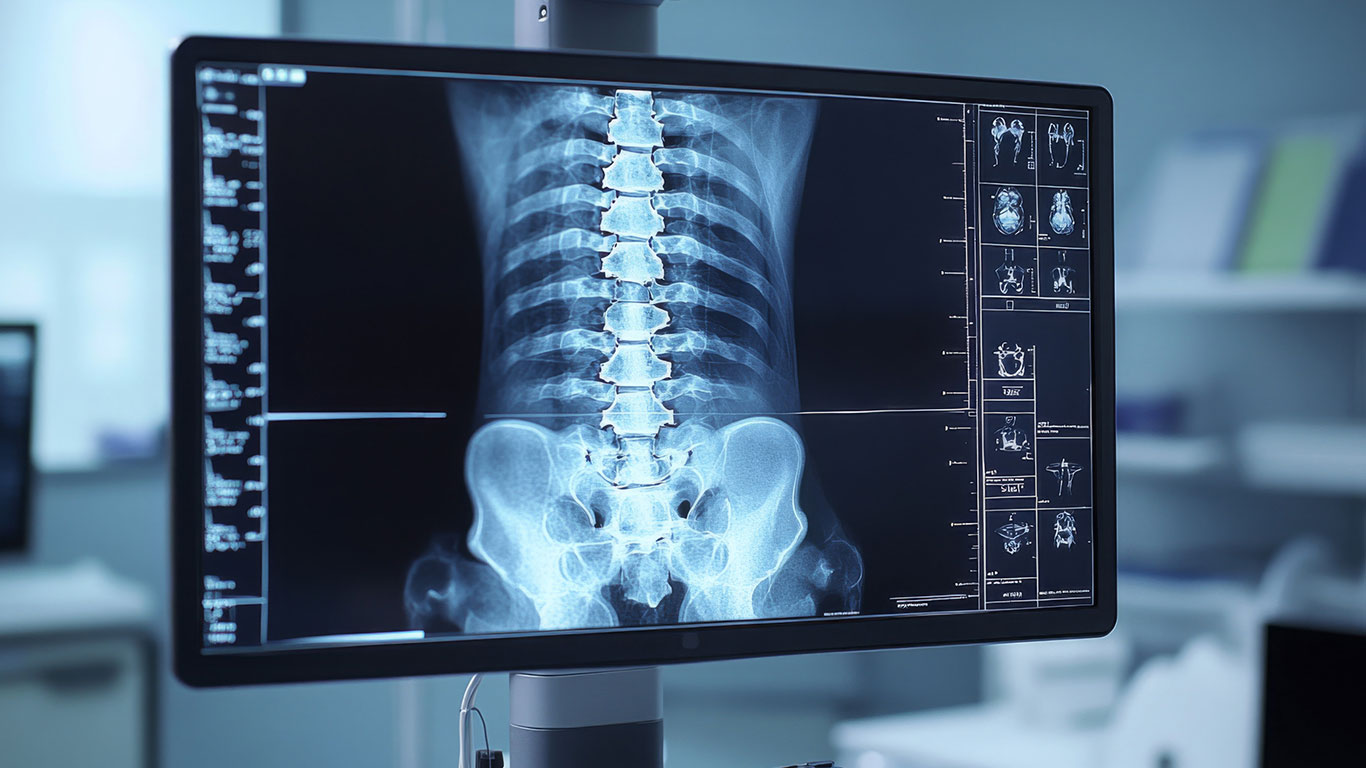

Spinal Tumour Surgery: Stabilising T4 Fractures with Carbon Fibre Pedicle Screws Before Radiotherapy

For those suffering from chronic back pain, limited mobility or conditions such as degenerative disc disease, spine fusion may be the solution to help you regain function and live pain-free. Spine fusion is a surgical procedure that stabilises the vertebrae in the spine, reducing motion between them and alleviating discomfort caused by worn-out discs or […]